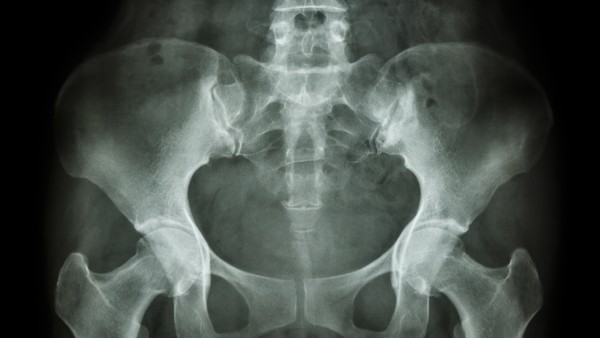

隨著滑膜反復(fù)發(fā)炎,會導(dǎo)致關(guān)節(jié)腔積液的增加。此時,可采用關(guān)節(jié)腔抽液、關(guān)節(jié)腔沖洗、關(guān)節(jié)腔灌注藥物治療。隨著疾病的進(jìn)展,疾病可能導(dǎo)致關(guān)節(jié)骨、軟骨等組織的損傷,導(dǎo)致關(guān)節(jié)功能障礙和關(guān)節(jié)畸形。

手術(shù)治療適用于這些關(guān)節(jié)結(jié)構(gòu)變化的群體,可能是永久性損傷或限制日常功能活動的患者的重要選擇。手術(shù)方法有很多選擇,可以根據(jù)具體情況選擇關(guān)節(jié)鏡、關(guān)節(jié)置換等治療。類風(fēng)濕性關(guān)節(jié)炎患者在日常生活中需要注意避免感冒,堅持適當(dāng)?shù)年P(guān)節(jié)運動。